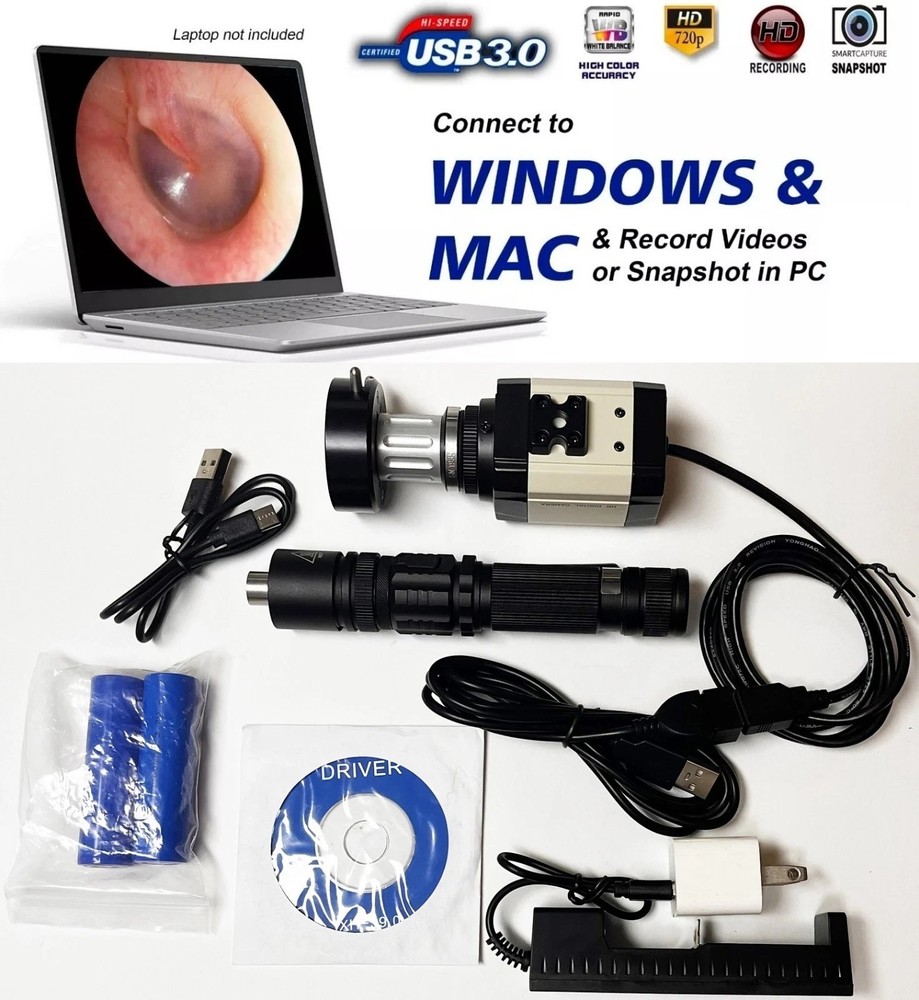

| Model | Endoscope |

| Flexibility | Rigid |

Check the listing for details. Rigid Endoscope Laparoscope HD USB Camera Head+Coupler+Light Source for ACMI. Condition: New – Open box, Made in United States. Listed at 375.00 USD. The entire item set can be sterilized by Gas (Only Endoscope is Soakable). Universal Endoscope Coupler Coupler End Receives the endoscope. Compatibility: STORZ, WOLF, OLYMPUS, ACMI etc. Endoscope Not Included.